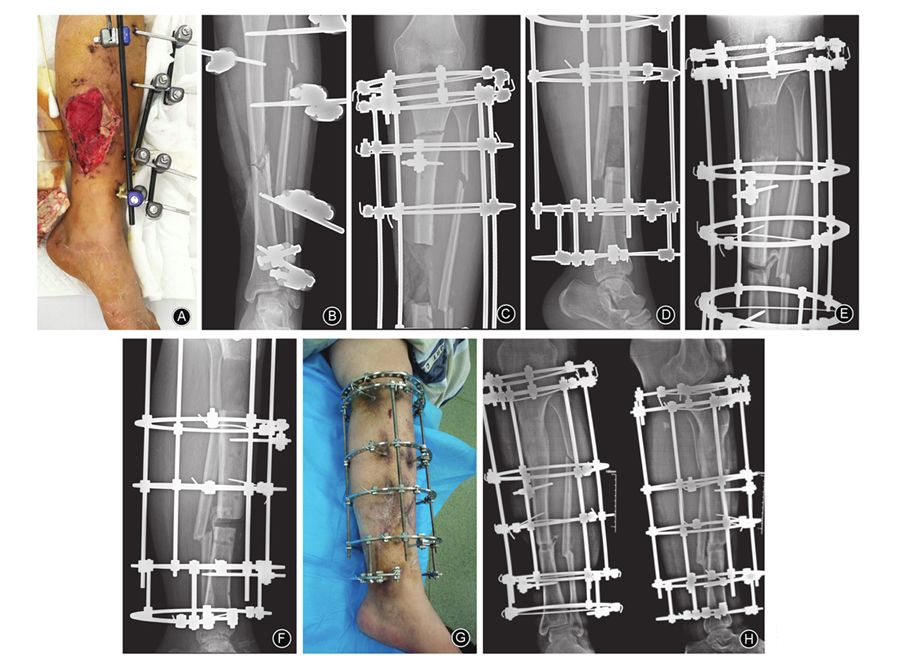

图2 男,22岁,车祸伤致左小腿开放性骨折 A 外固定架固定术后1个月,大体照片示左小腿中段内侧9 cm×8 cm皮肤缺损区,伴感染死骨形成 B 术前正位X线片示左胫骨无愈合征象 C,D 骨搬移术后1周,左胫骨正、侧位X线片示骨缺损约10 cm E,F 骨搬移术后4个月,正、侧位X线片示延长骨段矿化良好,断端对合,下肢力线无明显偏移 G 小腿内侧创面给予开放换药,骨搬移术后4个月大体照片示创面完全愈合 H 骨搬移术后9个月,正侧位X线片示骨搬移断端对合良好

术后每2周摄患肢正、侧位X线片,无一例发生骨化不良及提早骨化。本组31例患者中,28例骨断端一期经外固定持续轴向加压后骨性愈合(图1,图2);2例股骨、1例胫骨断端经二期植入髂骨松质骨、轴向加压后实现骨性愈合。骨愈合时间6~18.5个月,平均11.5个月,其中股骨愈合时间(12.59±5.40)个月,胫骨愈合时间(10.30±1.87)个月,两组比较差异无统计学意义(t=1.60,P=0.13)。